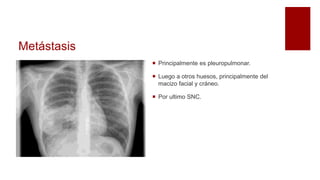

Metástasis

 Principalmente es pleuropulmonar.

 Luego a otros huesos, principalmente del

macizo facial y cráneo.

 Por ultimo SNC.